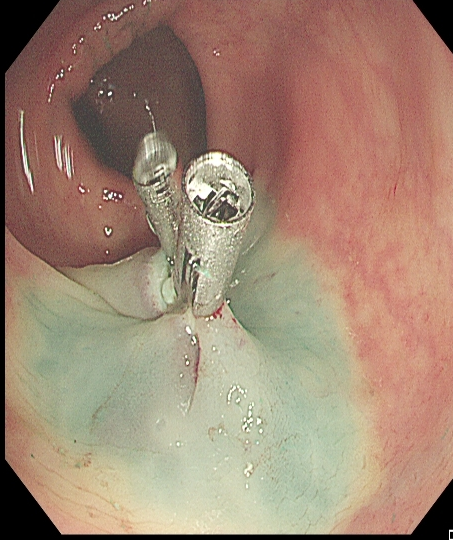

对于大型Ⅰp病变,除以上注意事项外,应采用热圈套方式切除,切除前应于蒂根部充分黏膜下注射(经内镜注射针将2~10 mLl万单位的肾上腺素+亚甲蓝+生理盐水混合液注射于黏膜下,边退针边注射),致使蒂部充分隆起,易于切除(图 3),切除过程中病变应避免接触肠壁,以免形成闭合回路,灼伤肠壁。

需要注意的是大型Ⅰp型息肉若蒂部较粗,则可能含粗大滋养血管,切除后极易出血。切除过程中可采用凝-切-凝的方式,减少出血风险。部分较大息肉,可采取分块切除方式,降低操作难度,但此法不利于病理评估。